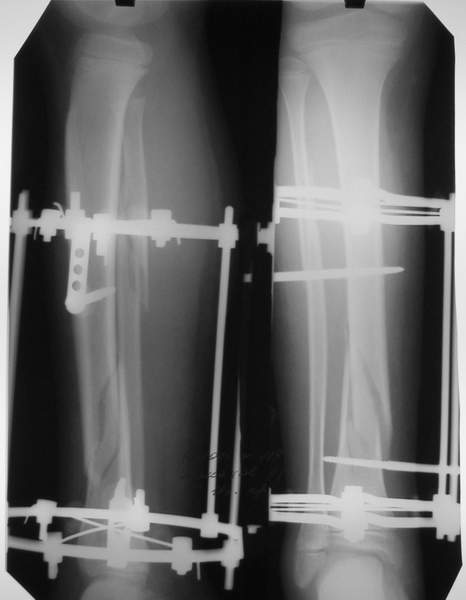

В аттачте № 3 - один из примеров полукольцевого аппарат...

Это уже я баловался.

Итог? Работы больше (по времени и

интраоп "подгонке"), срастается также, а особого преимущества по сравнению с

"чиста" кольцевым (вес, удобство ношения и пр.) - я, по крайней мере,

не нашел.

Теперь не балуюсь.

Может быть зря?

;-)